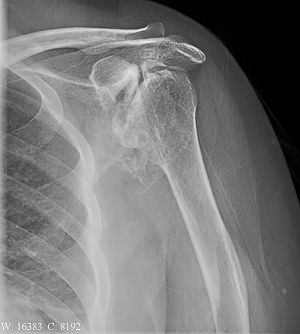

关节盂有破坏,肱骨头变形密度不均,关节间隙狭窄,软组织钙化,有外伤史,考虑创伤性关节炎可能性大,关节tb待排,建议ct。

左肱骨头及关节盂破坏畸形,密度增高外形不整,关节间隙显示不佳,考虑创伤性关节炎改变。